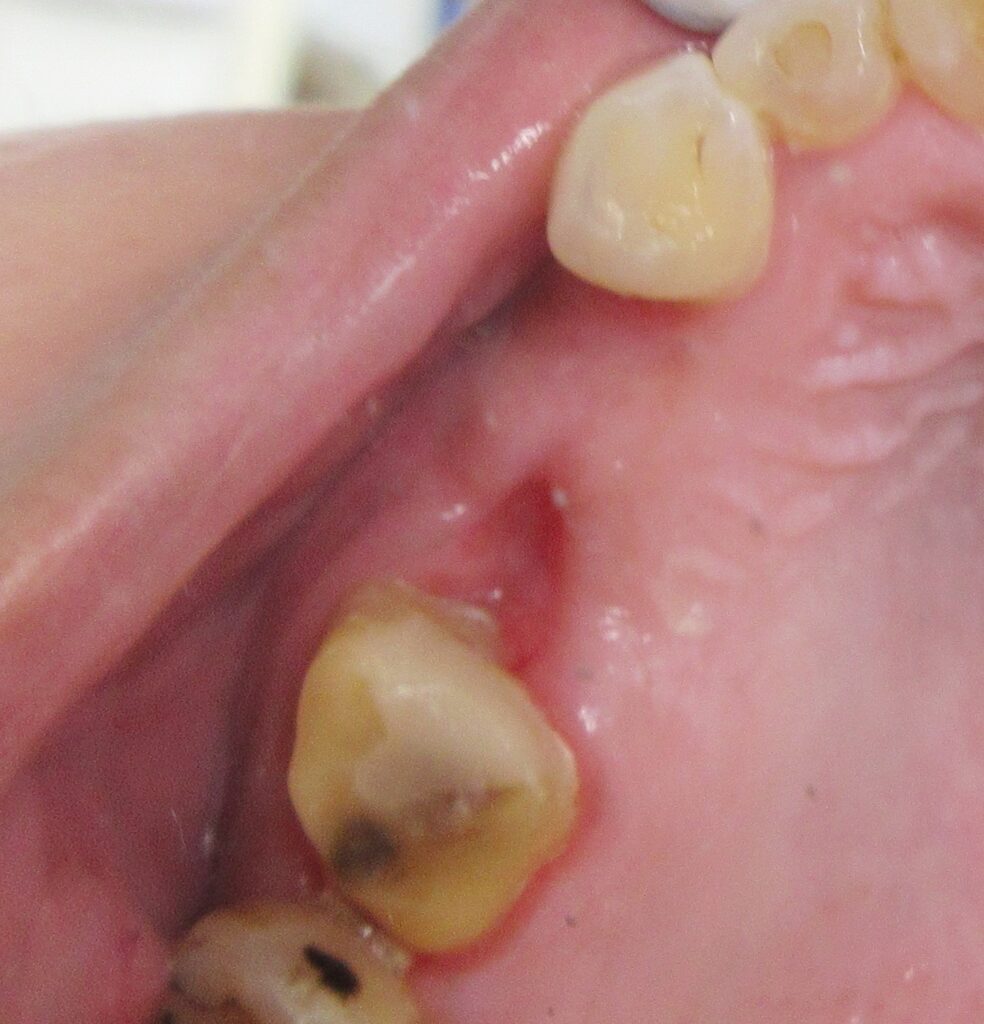

まずは右上4番目の歯茎から骨の部分までを穴開けパンチの要領で穴を開けていきます。

くりぬいた部分の歯肉を取り除き、次は骨に穴を開けていきます。